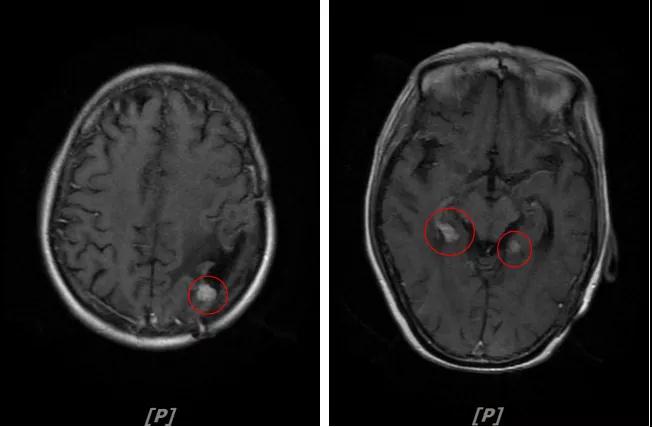

b.2014年3月全脑放疗结束后,予以LX方案治疗(拉帕替尼 1250mg qd+卡培他滨 1500mg bid)。每3个月规律复查,未见明显异常。下图为2014年6月患者行头颅增强MR检查,提示左顶叶脑转移瘤术后改变。

c.2015年2月患者因较严重的手足综合征(毒性分级3级),停卡培他滨(2015年2月中旬),给予单药拉帕替尼维持治疗,并加用阿那曲唑(1mg,qd)内分泌治疗。

每3个月规律复查,未见明显异常。如2015年8月 头颅MR检查,提示:左顶叶脑转移瘤术后放疗后改变,对比前片2015年3月10日相仿。

3.病情第2次进展: 2016年12月患者再次出现头痛症状

头颅增强MR:左侧顶枕叶见片状T1WI低信号、T2WI高信号影,增强后病灶边缘见局部斑片状强化改变,邻近脑膜轻度强化改变;右侧脑室三角区内侧见大小约8x14mm的结节影,T1WI低信号、T2WI等高信号,增强明显强化,灶周水肿明显;两侧脑室旁见片状异常信号,T1WI低信号,T2WI高信号,增强未见明显强化,余脑室、脑池、脑沟大小形态可,中线结构居中无移位

左顶叶脑转移瘤术后放疗后,左顶叶术区边缘强化灶;考虑肿瘤复发

右侧脑室三角区内侧转移瘤

两侧脑室旁云絮状异常信号,考虑放疗后改变

患者一线治疗的PFS为37个月。2017年1月,患者二线治疗为在原“拉帕替尼+阿那曲唑”基础上,加曲妥珠单抗治疗。患者头痛症状有所改善,病灶缩小,继续定期复查。